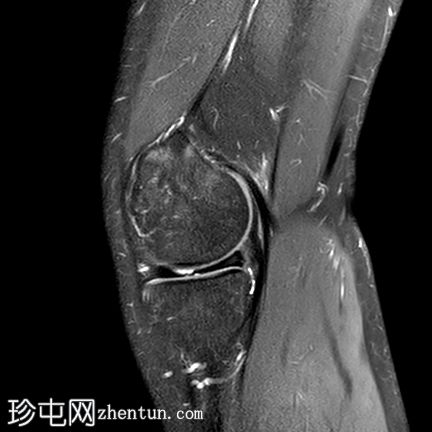

矢状位

PD脂肪抑制序列

内侧半月板(体部)内缘呈波浪状,符合半月板皱褶。

延伸至关节面的线状高信号,符合水平撕裂。

前交叉韧带(ACL)近端高信号提示部分撕裂。

股骨内侧髁后方关节积液及骨髓水肿。

半月板皱褶在矢状位图像上表现为膝关节半月板内缘呈波浪状。它与半月板撕裂的发生率增加无关,不应与半月板撕裂混淆,尽管在本病例中两者同时存在。